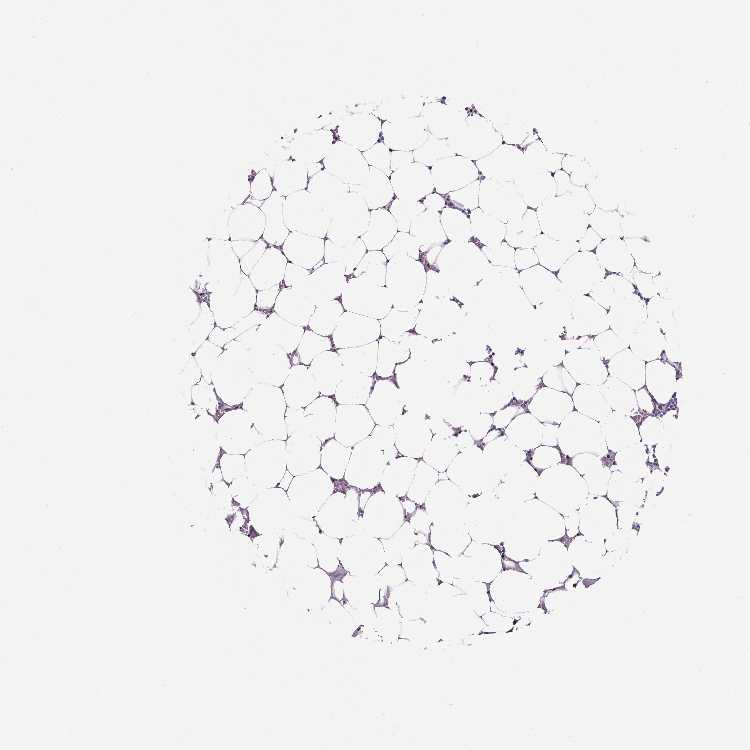

BONE MARROW - Antibody stainingi

Antibody staining in the annotated cell types in the current human tissue is reported as not detected, low, medium, or high, based on conventional immunohistochemistry profiling in selected tissues. This score is based on the combination of the staining intensity and fraction of stained cells.

Each image is clickable and will lead to virtual microscopy that enables deeper exploration of all samples and also displays staining intensity scores, fraction scores and subcellular localization as well as patient and tissue information for each sample.

Antibody HPA005533Antibody CAB068196Antibody CAB068197

Hematopoietic cells Not detectedLowNot detected